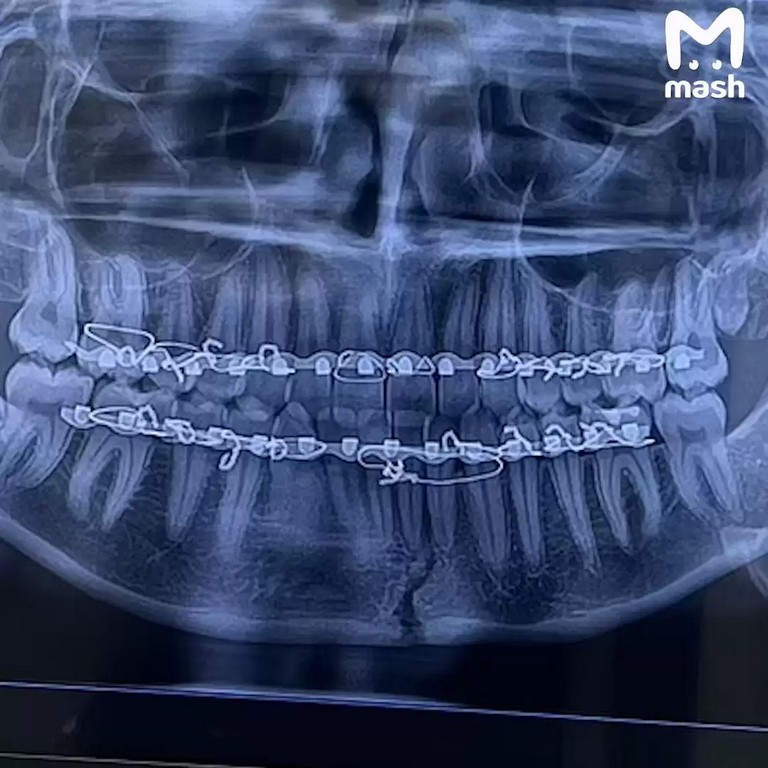

Лікарі, до яких звернулася дівчина, поставили невтішний діагноз: верхня і нижня щелепи буквально розділилися на дві частини.

“Я більше ніколи не буду їсти льодяники,” — зізналася Джаверія в одному з наступних відео, які вона вже знімала з лікарняного ліжка. Тепер її раціон обмежується лише рідкими стравами, а її посмішка поки що “захована” за металевими конструкціями, які фіксують щелепи.